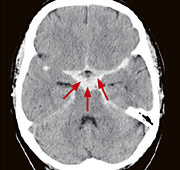

Abb. 1

Akut aufgetretener, heftigster Kopfschmerz. Das Computertomogramm zeigt eine Einblutung in den Liquorraum (SAB, Pfeile) nach Einriss eines Aneurysmas (krankhafte Gefässaussackung).

Die Computertomographie eignet sich aufgrund sehr kurzer Untersuchungszeiten insbesondere für die Notfalldiagnostik, zum Beispiel bei den akut auftretenden stärksten Kopfschmerzen einer Hirnblutung oder bei Schädelverletzungen. Sehr leistungsfähig ist die CT Angiographie, die eine detaillierte 3-D-Darstellung von Kopf- und Halsgefässen liefert, unter anderem bei Verdacht auf Gefässfehlbildungen oder -verschlüsse. Aber auch bei Erkrankungen der Schädelknochen und der Nasennebenhöhlen wird primär die Computertomographie eingesetzt.